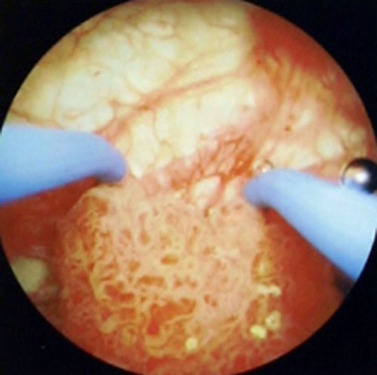

腔内泌尿外科彩色图谱(精)

作者 谷现恩//刘瑞强//闫治安